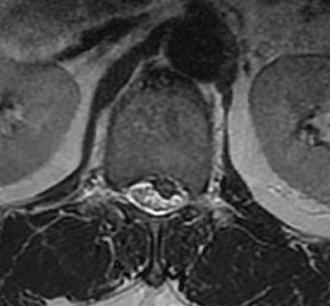

MRI

T2 Sagittal - myelogram

T1 Axial - see nerve root against white fat